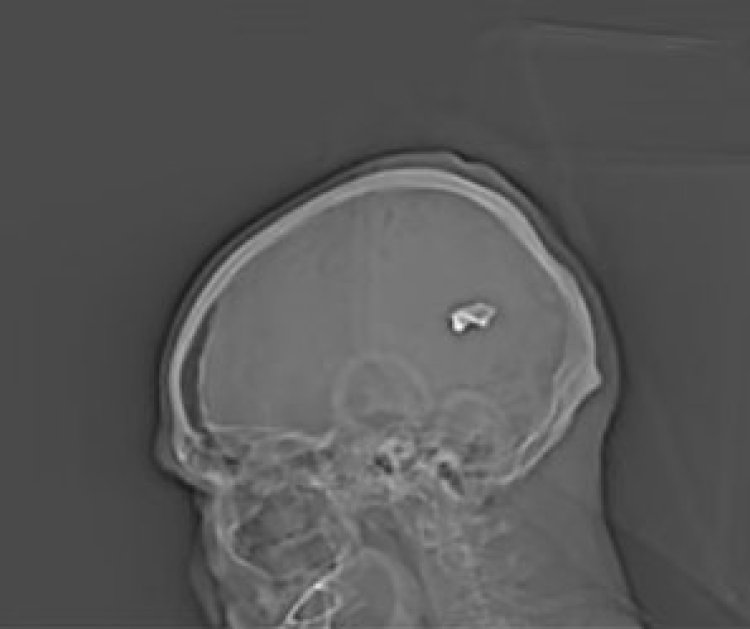

תצלומים נוספים, הוכיחו מקרים של שימוש בנשקים כבדים, ביניהם גם מכונות יריה וכלי נשק אוטומטיים בקליבר גבוהה כמו תותחי נ"מ ישנים. באחת התמונות שפורסמו ניתן לראות קליע שנורה באופן ישיר אל תוך חלקו האחורי של ראשו של מפגין, שעל פי עדויות הוצא ככל הנראה להורג על ידי כוחות המשטר.